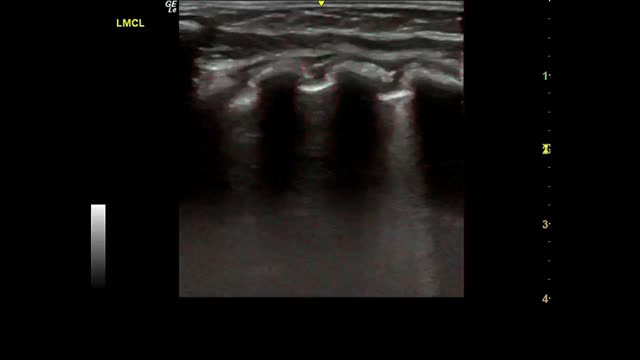

Fig. 2 shows the main findings of the LU imaging described in the study.